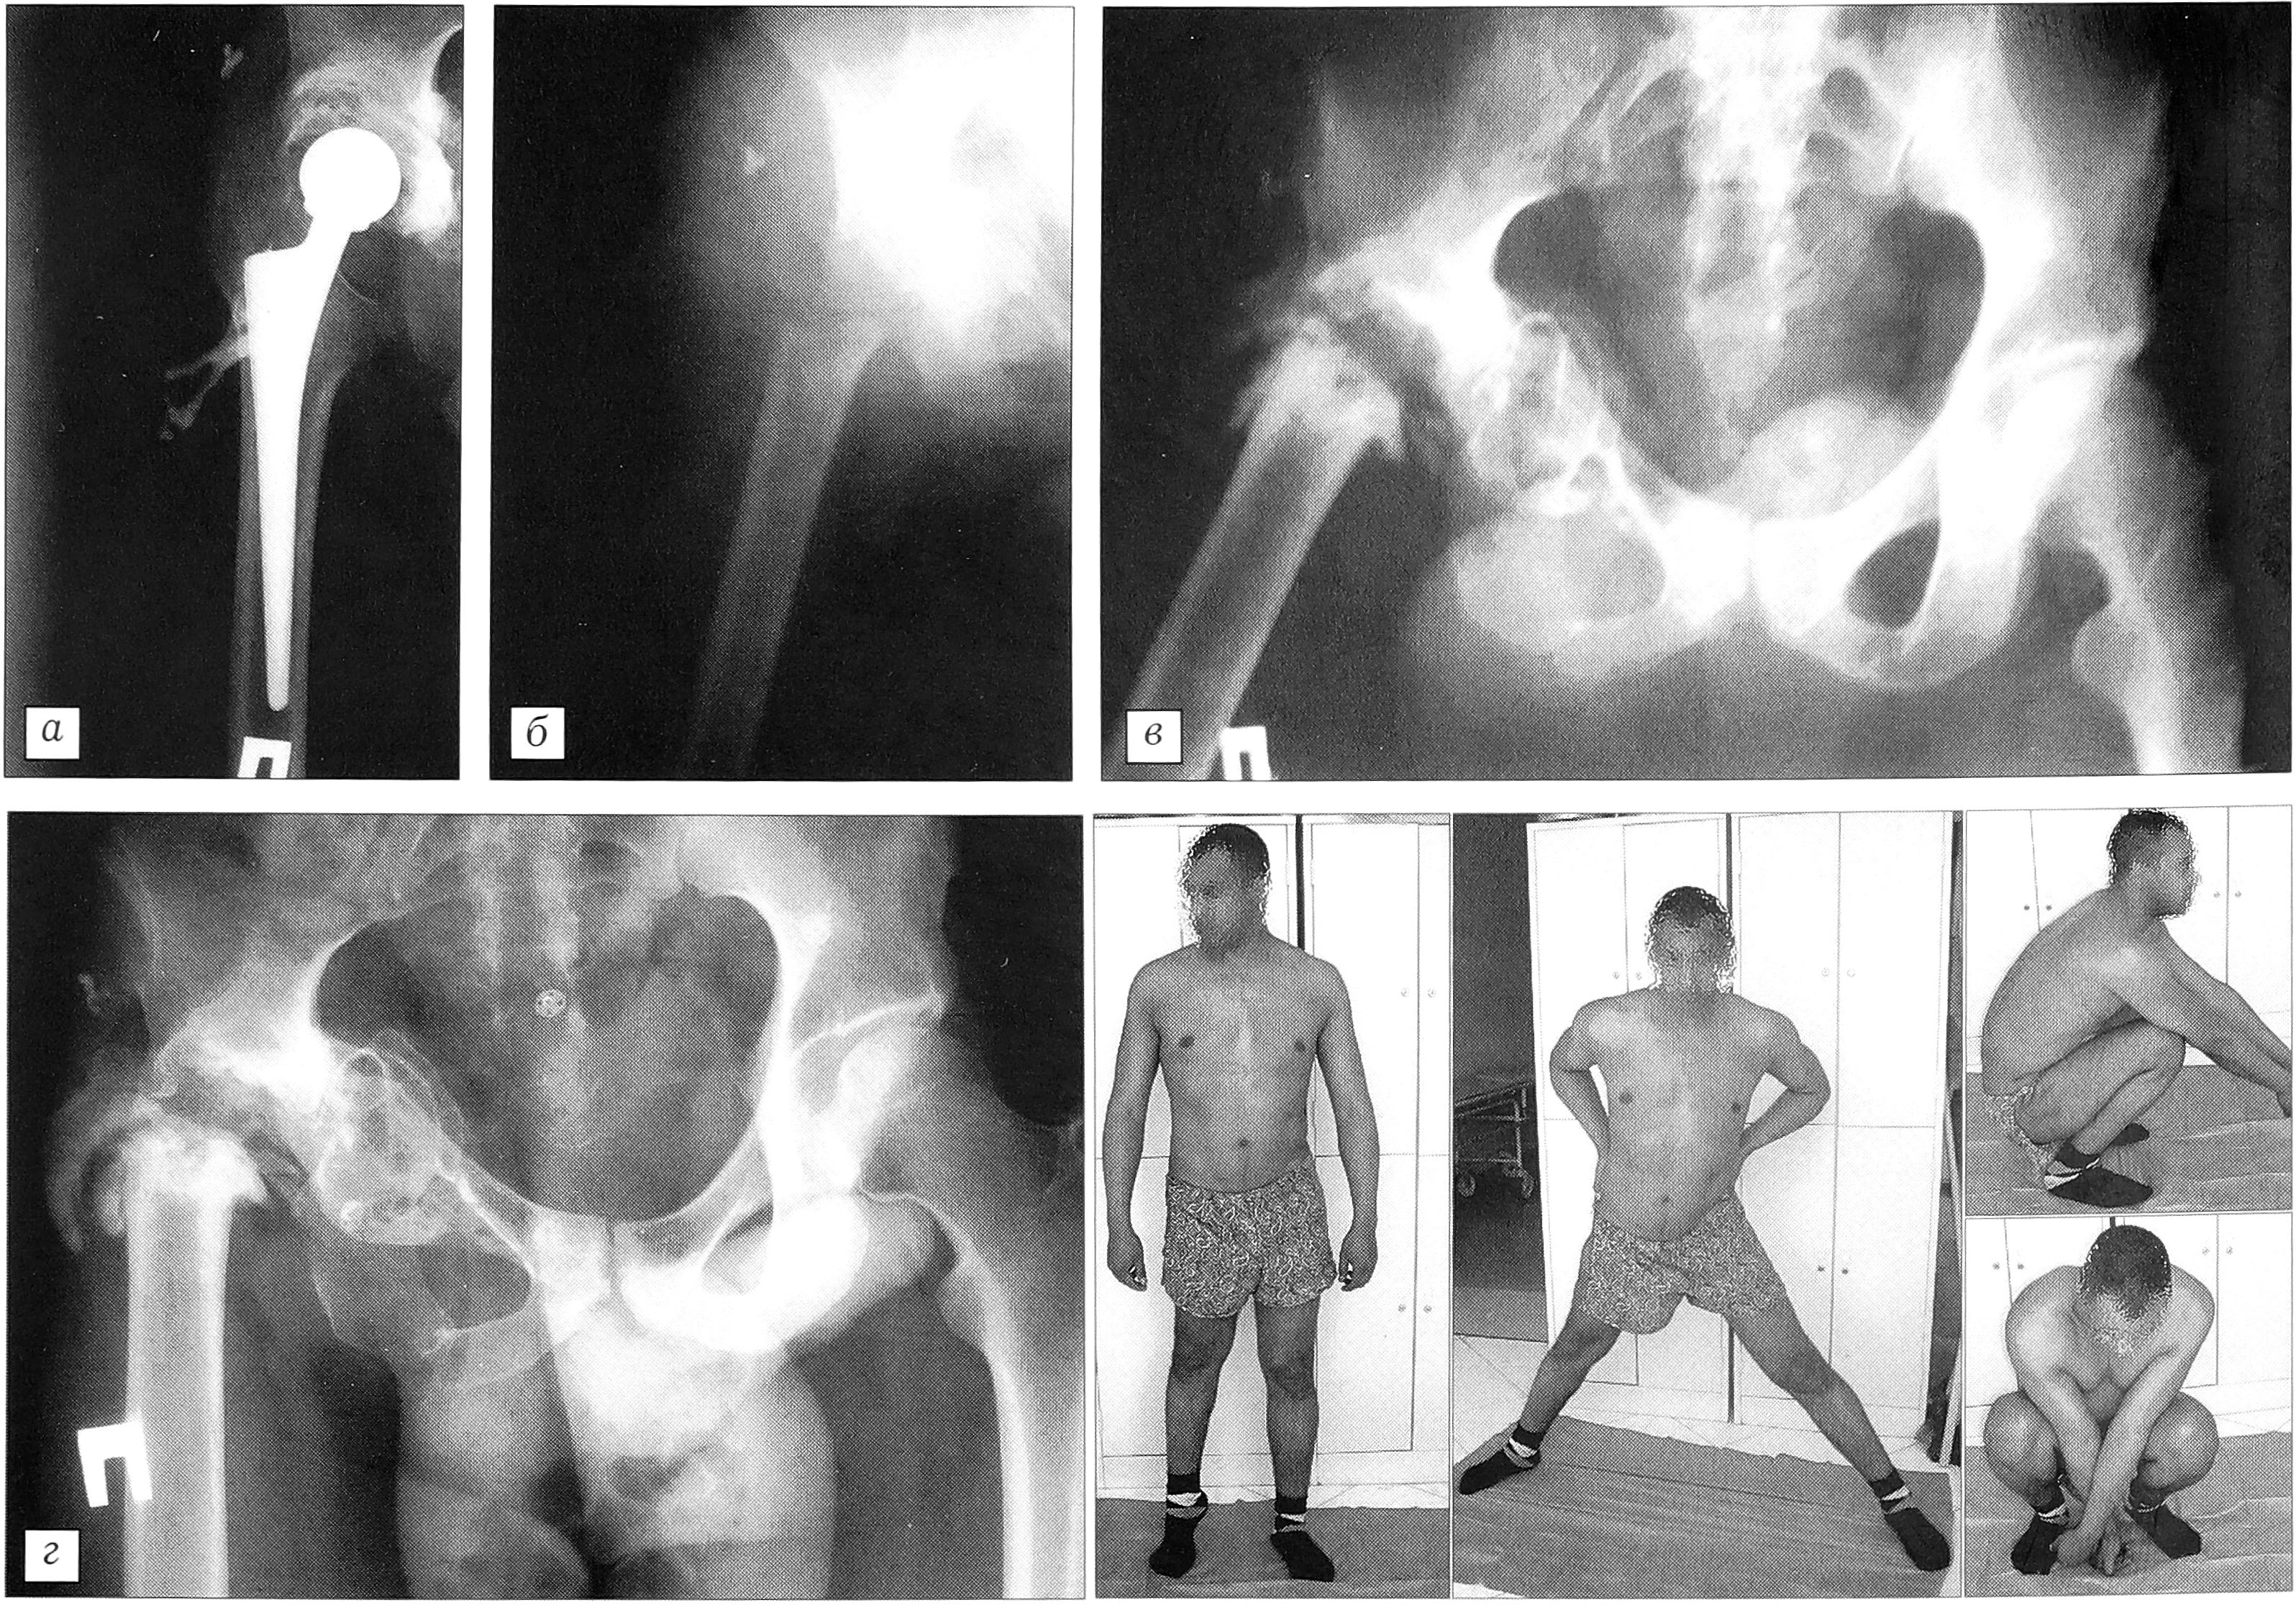

Через 6 мес после эндопротезирования поступил в нашу клинику. Произведено удаление нестабильного эндопротеза с резекционной фистулосеквестрнекрэктомией проксимального отдела бедра и вертлужной впадины. Проведен реабилитационный комплекс, включающий мероприятия, направленные на формирование опорного неоартроза (рис. 9, а—в).

Пациент наблюдается нами в течение 5 лет (рентгенологическая картина и функциональный результат представлены на рис. 9, г). 3 мес назад больному произведена компактотомия правого бедра с остеосинтезом стержневым аппаратом МКЦ. Укорочение правой нижней конечности в 6 см компенсировано (рис. 9, д).

Рис. 9. Больной М. 32 лет. а — фистулограмма при поступлении (через 6 мес после выполнения повторной резекционной фистулосеквестрэктомии проксимального отдела бедра с первичным эндопротезированием тазобедренного сустава протезом «Protek»: определяется затекание контрастного вещества по шейке эндопротеза в нестабильный вертлужный компонент; б — рентгенограмма, выполненная на следующий день после удаления нестабильного эндопротеза и резекционной фистулосеквестрнекрэктомии костей, образующих тазобедренный сустав; в — рентгенограмма через 2 года после операции: сформировавшийся неоартроз; г — рентгенограмма и функциональные возможности сформировавшегося неоартроза через 5 лет после операции; д — на этапе удлинения бедра в стержневом аппарате мкц.